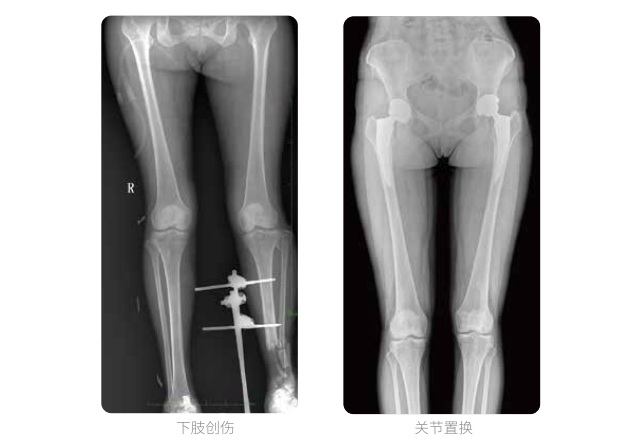

雙下肢臨床影像

普愛(ài)醫(yī)療動(dòng)態(tài)數(shù)字化X線攝影(動(dòng)態(tài)DR)可以整體顯示雙髖至雙踝關(guān)節(jié),直觀的展示因關(guān)節(jié)軟骨磨損和軟組織不平衡所造成的畸形及力線異常,全面對(duì)比了解雙下肢的病變情況。對(duì)于下肢矯正和人工關(guān)節(jié)置換術(shù)的術(shù)前計(jì)劃,術(shù)后觀察有著重要的臨床意義。